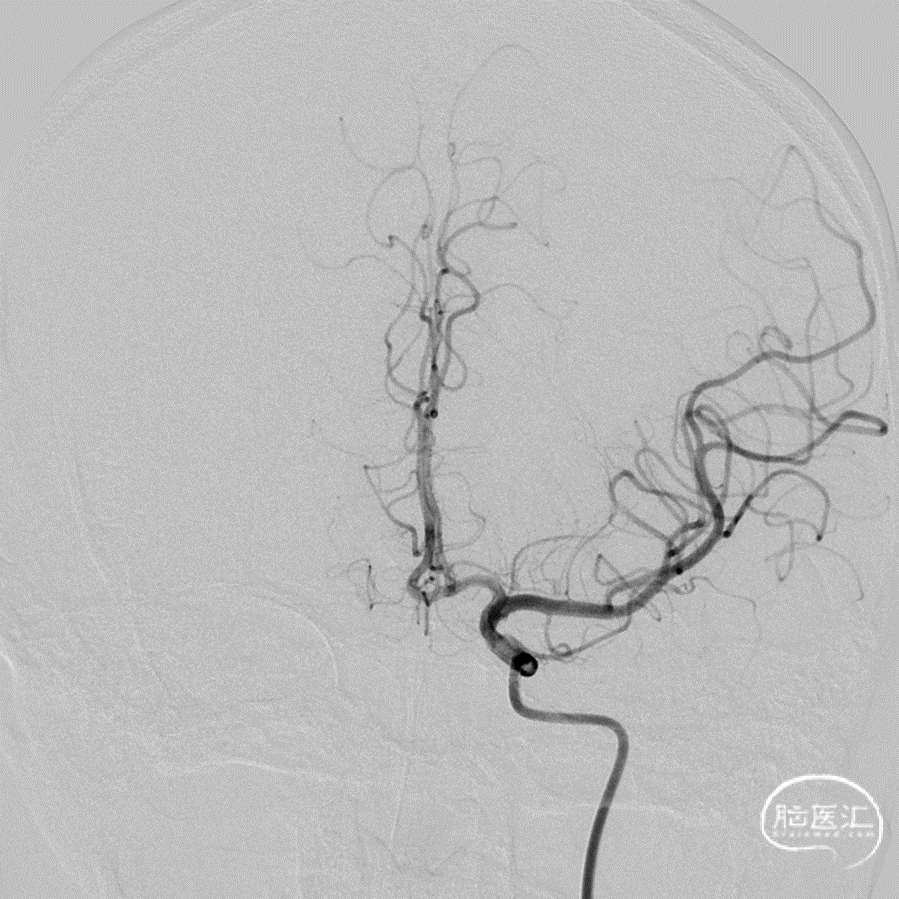

正位造影

侧位造影